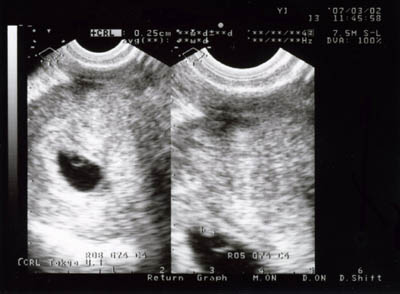

エコー写真を見ながら

「これが胎嚢でこれが卵黄嚢でこれが胎芽。CRLは2.5ミリだよ」

「胎芽の大きさのこと。まだ2.5ミリだけどちゃんと育ってるって。先生から

子宮の中もきれいだし、順調ですと言われたよ」

赤ちゃんはまだ胎芽だけど、順調に育っているみたいだ。

*エコー写真の左側

真ん中の黒い部分が胎嚢

その中の小さい白い部分が卵黄嚢

その上の小さい白い部分が胎芽

しっかり育っておくれ!